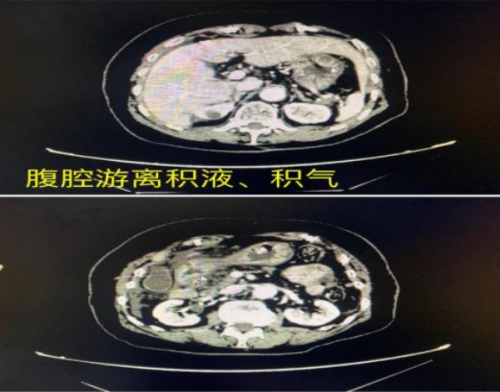

“患者入院时上腹部疼痛剧烈,呈刀割样、持续性,查体发现全腹肌紧张,全腹压痛、反跳痛,肠鸣音消失,胸腹部CT提示:腹腔游离积液、积气,考虑上消化道穿孔,穿孔点考虑位于胃窦部、十二指肠球部水平。”据急诊科副主任邵启兵介绍,病情紧急,医院马上开通绿色通道,在全麻下行腹腔镜胃窦穿孔修补+肠粘连松解术,术程顺利,术后转入急诊ICU严密监护治疗,经过精心治疗和护理,患者病情趋于平稳,于术后第2天停用呼吸机拔除气管插管,转入普通病房。